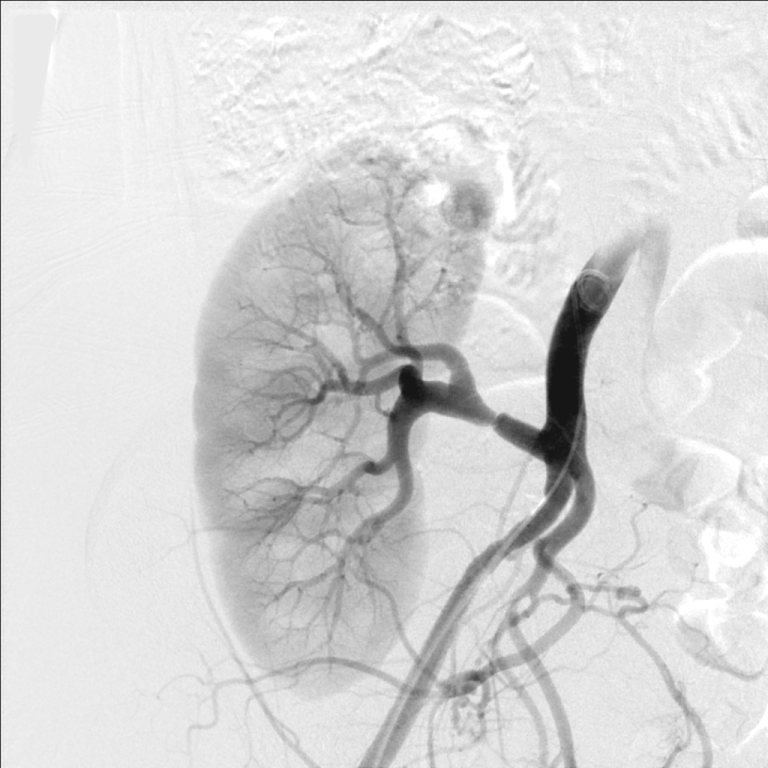

The patient was referred for renal angiography, which revealed a focal web-like stenosis in the mid portion of the transplanted renal artery (Figure 1). A Fractional Flow Reserve (FFR) wire was advanced through the stenosis and a 45 mmHg gradient was noted across the lesion. Subsequently, a 5 × 20 mm RX Viatrac 14 Plus balloon (Abbott Vascular, Inc., CA, US) was crossed and inflated to its nominal pressure (Figure 2). Post-angioplasty (Figure 3), the systolic gradient across the stenosis decreased to 25 mmHg. More aggressive dilatations were not performed because of the proximity of the stenosis to the bifurcation of the renal artery. A decrease in the blood pressure was noted in the recovery room and remained controlled without antihypertensive therapy in the subsequent visits.

Figure 1: Unselective iliac artery angiography, using a pigtail catheter, showing the transplanted renal artery stenosis in its mid portion. View Figure 1